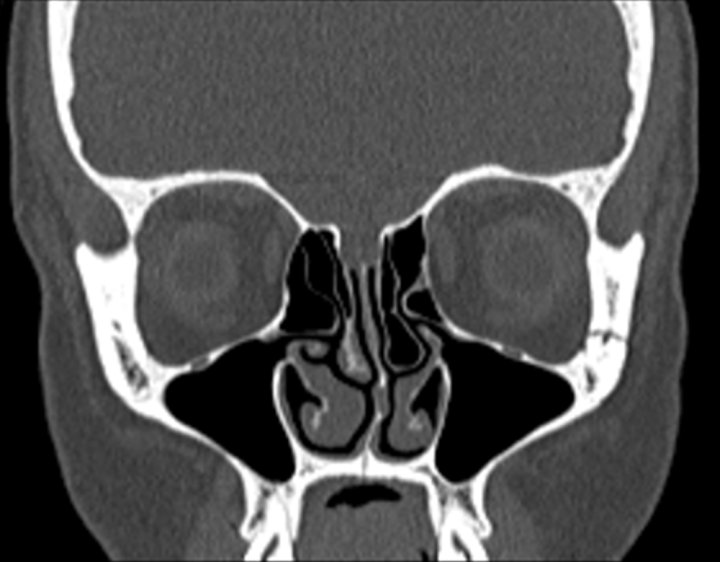

Click any image for labels.